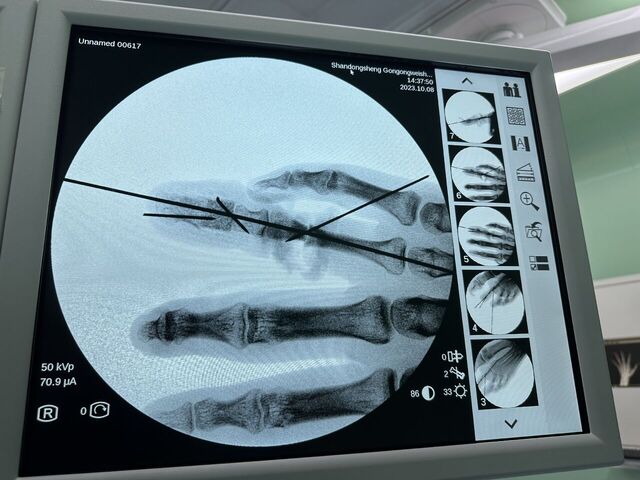

昨天的手术。